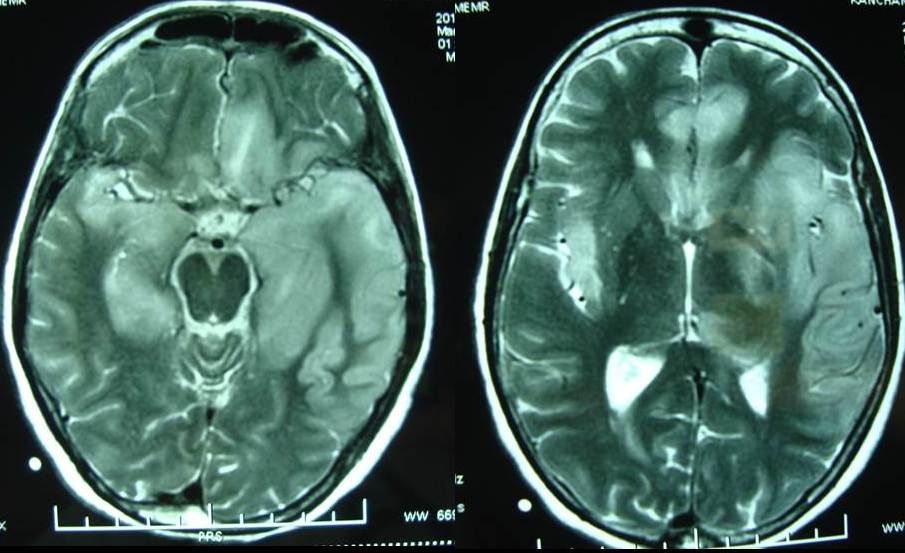

Bác sĩ có thể chẩn đoán dựa trên bệnh sử và khám thực thể. Các xét nghiệm, chụp cắt lớp vi tính (CT), chụp cộng hưởng từ (MRI) và điện não đồ có thể được thực hiện để hỗ trợ chẩn đoán và loại trừ các bệnh khác. Phương pháp chọc dò tủy sống thắt lưng sẽ được thực hiện để kiểm tra dịch não tủy. Sinh thiết não cũng có thể được tiến hành để thực hiện bước chẩn đoán cuối cùng.